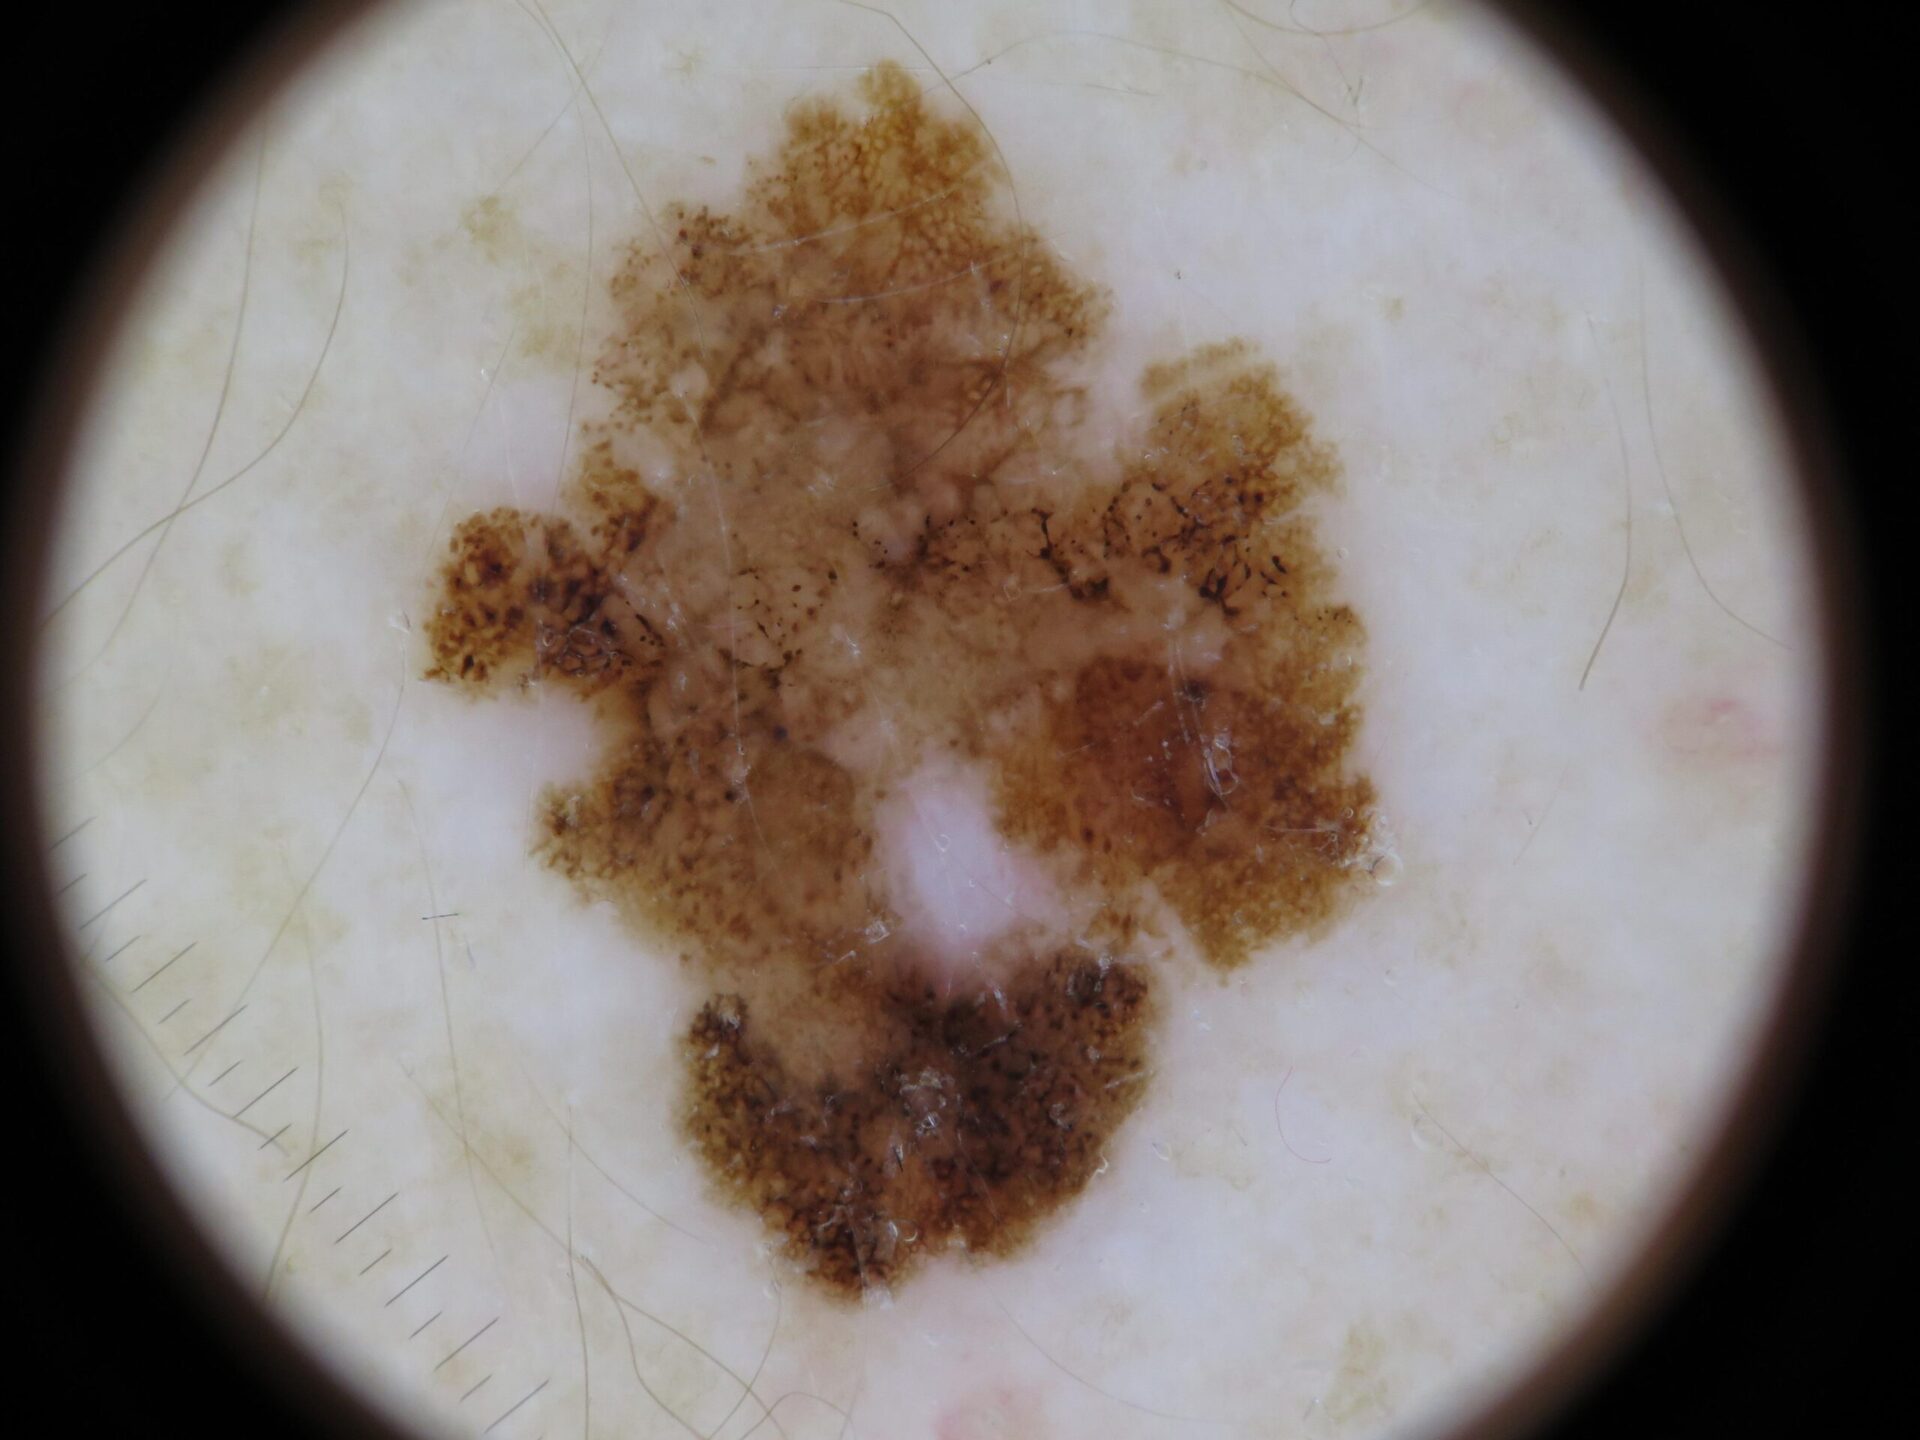

Actinic Keratosis (AK) Photos

Actinic keratosis on head or neck. Photo: International Skin Imaging Collaboration at isic-archive.com

Actinic keratosis on posterior torso. Photo: International Skin Imaging Collaboration at isic-archive.com